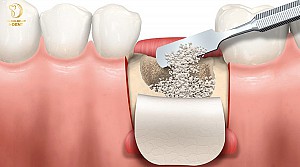

Trước tiên, các bác sĩ tiến hành mở vạt lợi để tiếp xúc vào xương hàm thông qua 3 đường rạch gồm một đường rạch dọc niêm mạc sống hàm (vùng mất răng) và hai đường rạch đứng từ phía hai đầu đường rạch đến ngách tiền đình sao cho vạt hình thành một đáy hình thang và có đủ độ rộng để thao tác các bước tiếp theo.

Sau đó, bác sĩ sẽ sử dụng cây bóc tách thích hợp để bóc tách vạt niêm mạc màng xương để lộ ra vùng cần phẫu thuật rồi rạch đường giảm căng.

Dùng mũi khoan chuyên dụng để khoan thủng vỏ xương, tạo các điểm chảy máu rồi trộn bột xương với máu bệnh nhân (hoặc với nước muối sinh lý) rồi đặt bột xương đã trộn vào bề mặt xương hàm theo khối lượng thích hợp. Cuối cùng đặt màng che phủ bột xương tại vùng cần phẫu thuật và cố định màng.